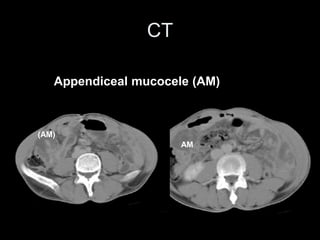

Appendiceal mucocele (AM)

(AM)

AM

CT